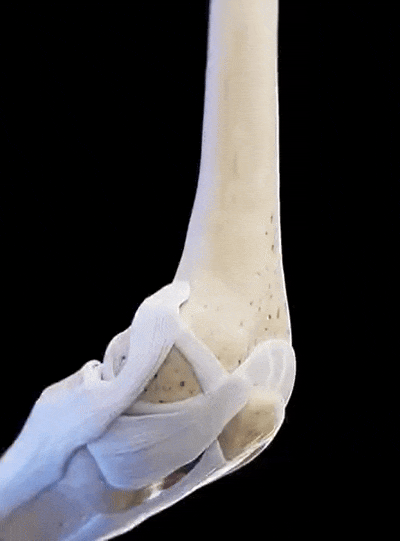

По време на прегледа откриваме ясни признаци на дегенерация на ставите.

❌ Хирургически намеси са необходими, ако ставата напълно откаже. Лекарите извършват операция и заменят ставата с ендопротеза.

При пълна деградация на ставата операцията е неизбежна. След това еластичността на тъканите никога няма да бъде същата.